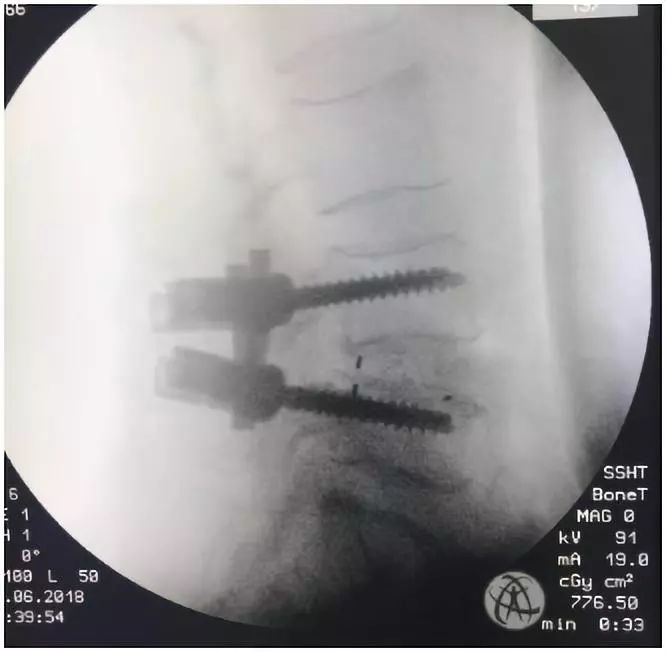

何主任通过屏幕看到椎弓根重建图像的准确位置,然后将椎弓根螺钉如“小李飞刀”一般,精准的植入了腰4、腰5椎体内~

手术大获成功~虽然只用了2小时,但术中的一举一动,都灌注了何升华主任及其团队的细心和认真,他们的严谨杜绝了手术的零失败。我醒来的时候已经躺在病床上,感觉像睡了一场午觉,手术居然就做完了~不自觉地抖了抖腿,可以动了!

吴老太太的案例是深圳市中医院骨伤科在全市中医系统内率先应用术中三维C型臂导航技术进行的“ “腰椎椎弓根内固定术”。三维实时导航,极大地增加了腰椎手术患者的安全性,使得该科椎弓根螺钉植入技术从此迈入零失误率的历史性阶段。